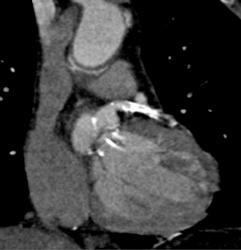

LAD Plaque Without Stenosis of Note